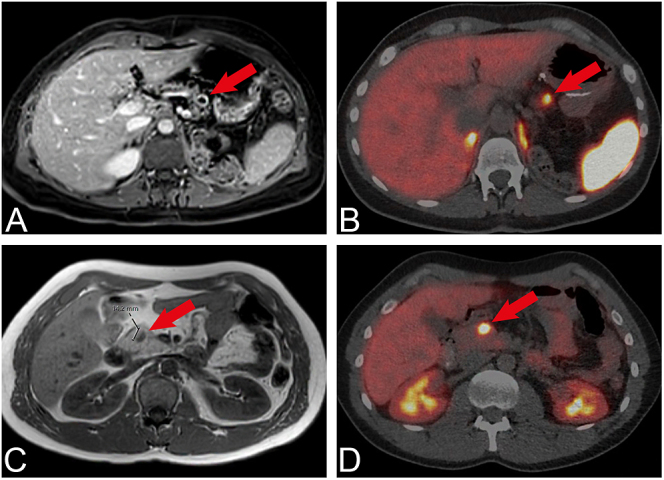

Pancreatic neuroendocrine tumours (PanNETs) significantly impact life expectancy in multiple endocrine neoplasia type 1 (MEN1). Both solid and cystic pancreatic lesions are observed in MEN1, yet limited research has been focused on cystic lesions in MEN1. While solid PanNETs are generally considered to have an indolent course, the natural course of cystic lesions remains unclear. This study aims to provide more insights into the natural course of cystic PanNETs in MEN1. Patients with MEN1 and radiologically suspected PanNETs, treated at UMC Utrecht and Radboudumc between 2010 and 2023, were included. In the first part, we examined the characteristics of patients with tumours visible on imaging scans. In the second part, we investigated outcomes of pathological examinations, following resection of these lesions. A total of 136 patients were included, comprising 60 men and 76 women. The median follow-up was 5.1 years. [68Ga]Ga-DOTATOC PET/CT scans showed that both cystic and solid lesions demonstrated [68Ga]Ga-DOTATOC PET/CT uptake. The median growth of cystic and solid PanNETs was similar. Pathological examination of 38 resected tumours confirmed that cystic lesions identified on imaging were indeed PanNETs. Cystic lesions had a median diameter of 26 mm at the time of resection, compared to 18 mm for solid lesions, with comparable Ki-67 indices and mitotic counts. We conclude that cystic and solid PanNETs in MEN1 patients appear to be morphological variations of the same entity, suggesting that similar management approaches should be considered.